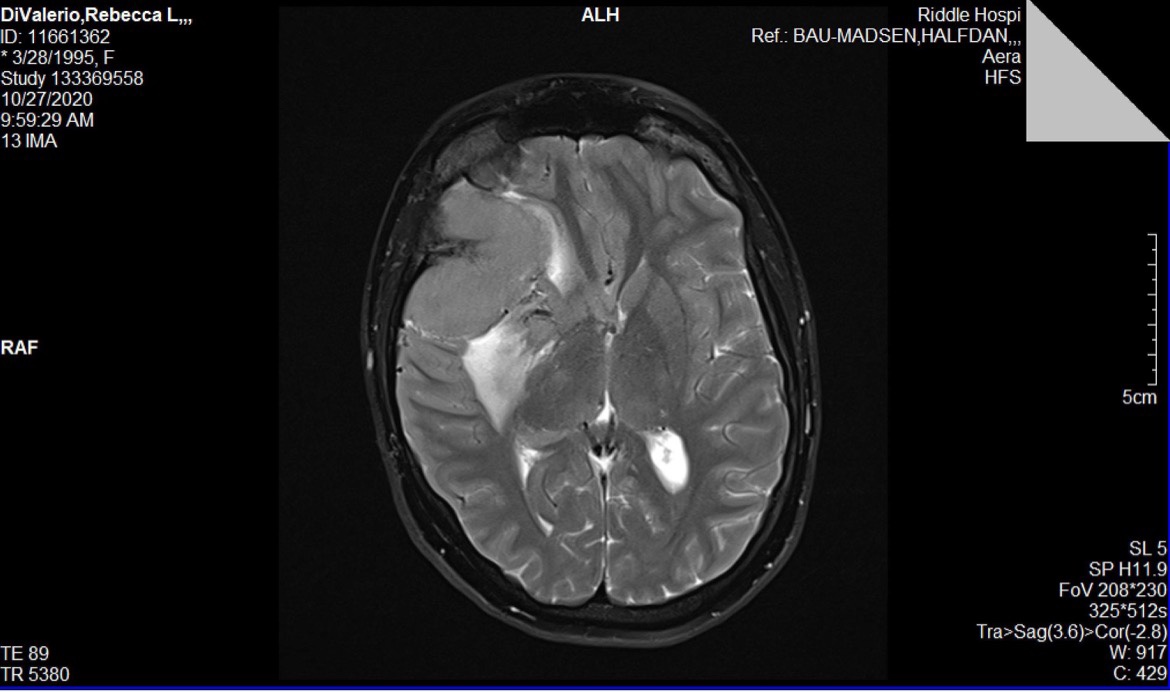

I added a photo of how big my tumor was for reference.